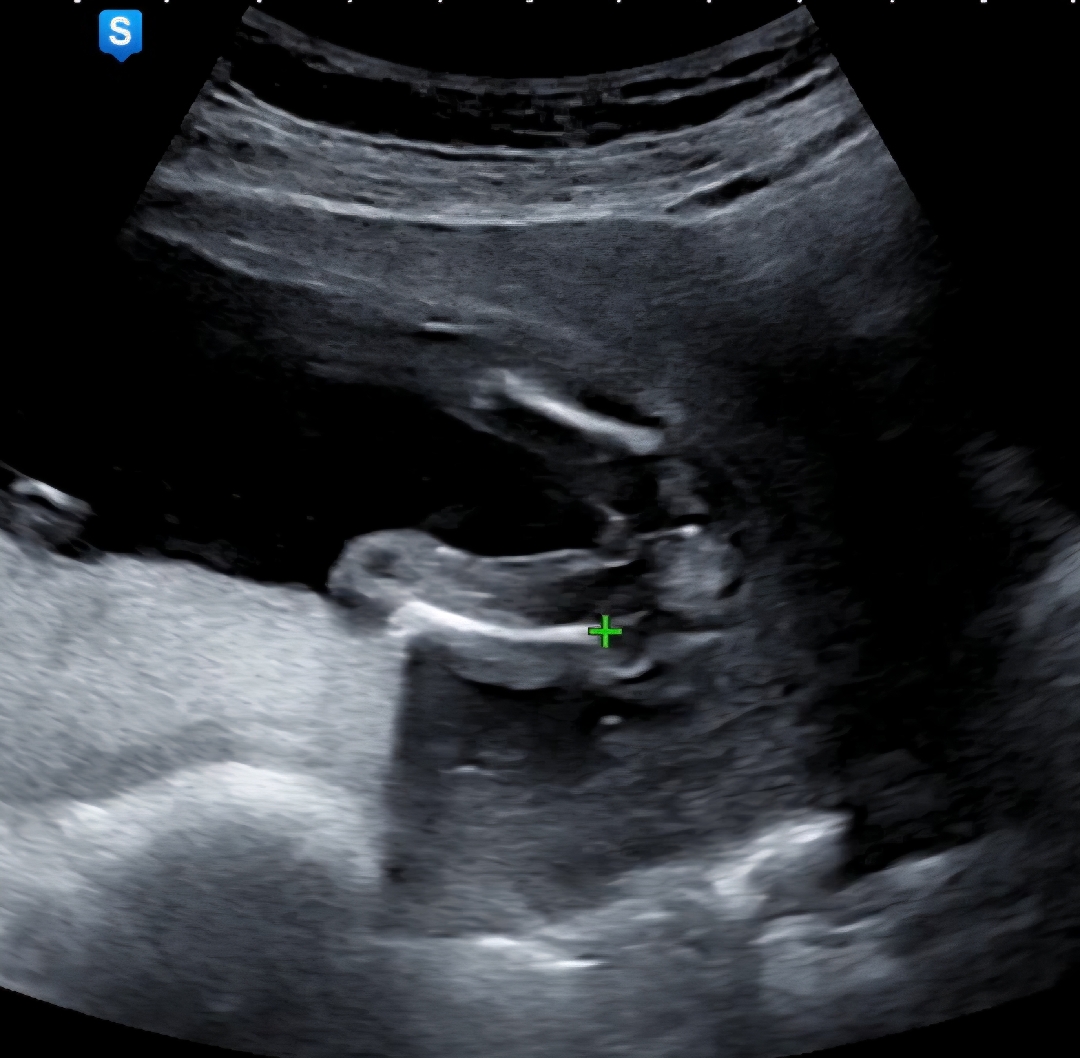

16주 5일, 성별 봐주세요!

딸이겠죠? 반전이 있을까요?

완전 딸인 것 같아요ㅎㅎ 아들은 저렇게 매끈하지 않더라구요